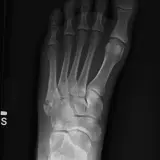

Over 2,100 interactive radiology cases, curated by radiologists for your level of training. Scroll, window, and view cases full screen — just like on PACS. Click linked findings in each writeup to jump straight to them on the image. Cases include sample reports, a focused discussion section, original illustrations, and videos.

Des cas entièrement interactifs avec les outils attendus d'un PACS — défilement, fenêtrage, zoom, déplacement, mesures, ROI et mode plein écran.

Des annotations détaillées mettent en évidence les résultats clés directement sur les cas. Cliquez sur les résultats liés dans les descriptions de cas pour accéder à leur emplacement exact sur l'examen.